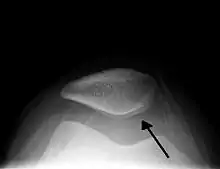

Image radio d'une hydarthrose du genou.

L’hydarthrose est l'accumulation anormale de liquide, spécialement de synovie, dans une articulation[1]. Cela survient essentiellement par augmentation de la sécrétion de synovie.

Elle est souvent localisée au genou (présence du signe du glaçon) et peut évoluer en kyste poplité.